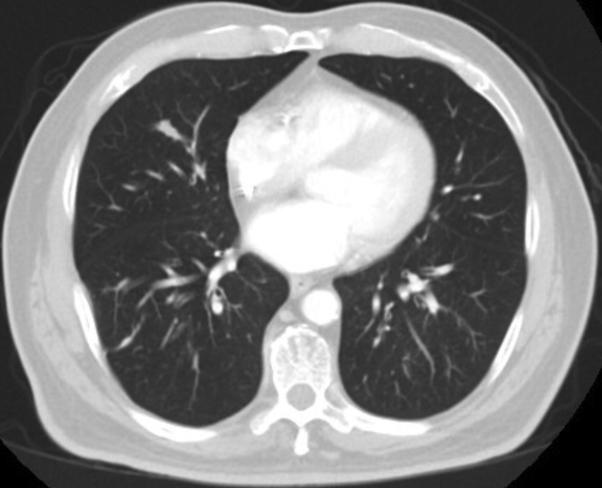

Complete pathologic response of metastatic cutaneous squamous cell carcinoma and allograft rejection after treatment with combination immune checkpoint blockade.

JAAD Case Rep. 2017 Sep 8;3(5):412-415. doi: 10.1016/j.jdcr.2017.06.005. eCollection 2017 Sep.

DOI:10.1016/j.jdcr.2017.06.005

PMID:28932782

原文链接:https://pmc.ncbi.nlm.nih.gov/articles/PMC5594230/